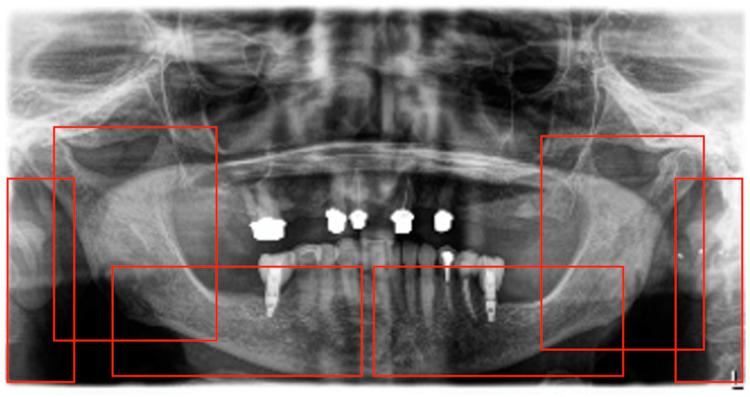

Osteoporosis, a systemic skeletal disorder, is expected to affect 60% of women over 50. While dual-energy X-ray absorptiometry (DXA) scans are the current gold standard for diagnosis, they are typically used only after fractures occur, highlighting the need for early detection tools. Initial studies have shown panoramic radiographs (PRs) to be a potential medium, but these have methodological flaws. This study aims to address these shortcomings by developing a robust AI application for accurate osteoporosis identification in PRs. A total of 348 PRs were used for development, 58 PRs for validation, and 51 PRs for hold-out testing. Initially, the YOLOv8 object detection model was employed to predict the regions of interest. Subsequently, the predicted regions of interest were extracted from the PRs and processed by the EfficientNet classification model. The model for osteoporosis detection on a PR achieved an overall sensitivity of 0.83 and an F1-score of 0.53. The area under the curve (AUC) was 0.76. The lowest detection sensitivity was for the cropped angulus region (0.66), while the highest sensitivity was for the cropped mental foramen region (0.80). This research presents a proof-of-concept algorithm showing the potential of deep learning to identify osteoporosis in dental radiographs. Furthermore, our thorough evaluation of existing algorithms revealed that many optimistic outcomes lack credibility when subjected to rigorous methodological scrutiny.

骨质疏松症是一种全身性骨骼疾病,预计50岁以上的女性中有60%会受其影响。虽然双能X线吸收测定法(DXA)扫描是目前诊断的金标准,但通常仅在骨折发生后才使用,这凸显了早期检测工具的必要性。初步研究表明全景X线片(PR)是一种潜在的手段,但这些研究存在方法上的缺陷。本研究旨在通过开发一种强大的人工智能应用程序来解决这些缺点,以在PR中准确识别骨质疏松症。总共348张PR用于开发,58张PR用于验证,51张PR用于保留测试。最初,采用YOLOv8目标检测模型来预测感兴趣区域。随后,从PR中提取预测的感兴趣区域,并由EfficientNet分类模型进行处理。在PR上进行骨质疏松症检测的模型总体灵敏度为0.83,F1分数为0.53。曲线下面积(AUC)为0.76。检测灵敏度最低的是裁剪后的角部区域(0.66),而最高灵敏度是裁剪后的颏孔区域(0.80)。本研究提出了一种概念验证算法,展示了深度学习在牙科X线片中识别骨质疏松症的潜力。此外,我们对现有算法的全面评估表明,许多乐观的结果在经过严格的方法学审查后缺乏可信度。